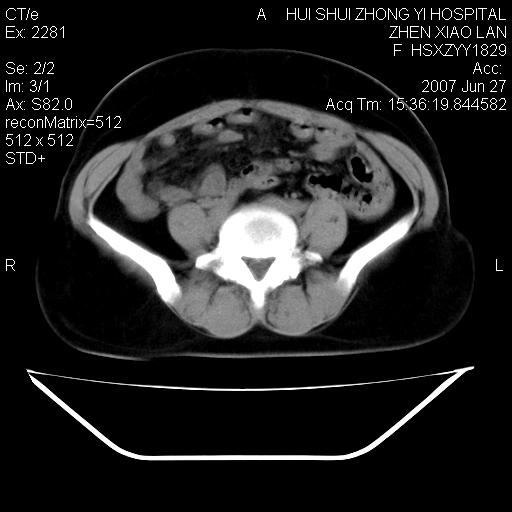

以下是引用还珠格格在2007-6-28 15:15:00的发言:[br]子宫明显增大,偏向盆腔右侧,密度均匀,和子宫同密度, 考虑 子宫肌瘤可能性大 建议增强 除外子宫平滑肌肉瘤。

以下是引用dyqct在2007-6-28 15:41:00的发言:[br]考虑多发子宫肌瘤可能性大,建议进一步增强检查。